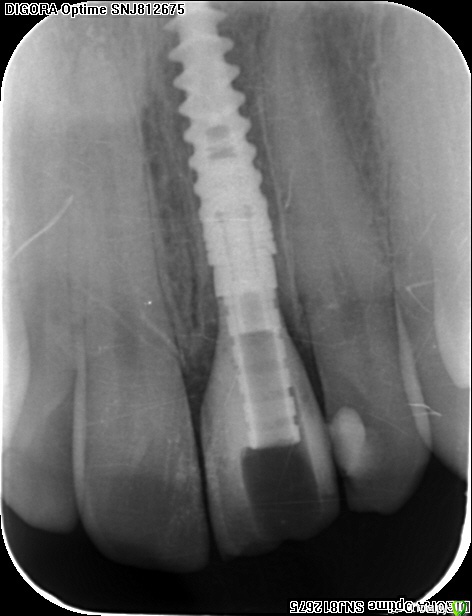

an_ver Опубликовано 15 декабря, 2015 Поделиться Опубликовано 15 декабря, 2015 Травма 21, немного сместился,удаление,имплантация SPI 4.2*13,ГенОсс+ ауто со сверла,для временной коронки использован свой зуб)),немного укоротили реж.край,чтоб не травмировать,унифлекс 5/0 18 Ссылка на комментарий